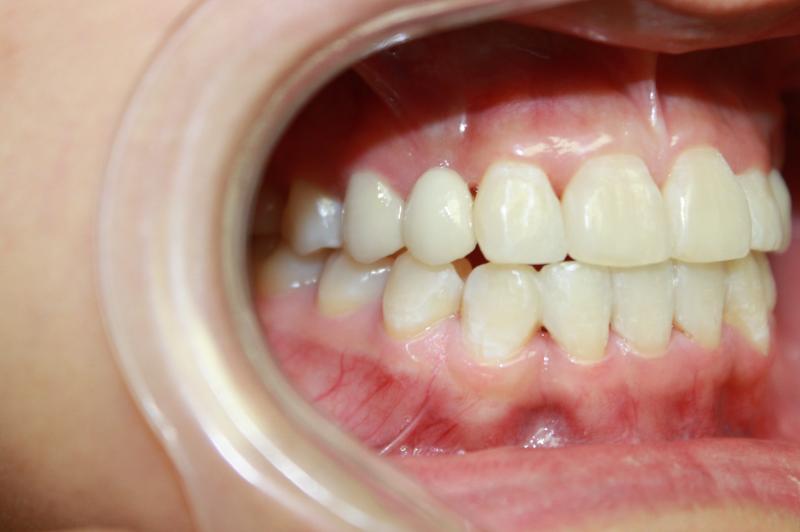

INVISALIGN - 13 months, 1 lower tooth removal, 1 series of aligners to align teeth and create the proper amount of space for 2 cantilever bridge to replace congenitally missing cuspids. COSMETIC DENTISTRY - 2 porcelain cantilever bridges and cosmetic bonding to reshape incisors and close gingival spaces. TOTAL TREATMENT TIME, 15 months

Cosmetic Dentistry, Mid-line Asymetry, Missing Teeth, Severe Crowding